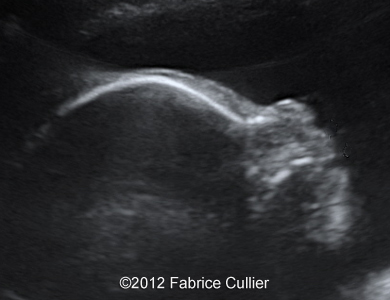

Image 6, 7 : 2D sagital views of the face at 29 weeks shows retrognatism with normal nose bones.

5

6